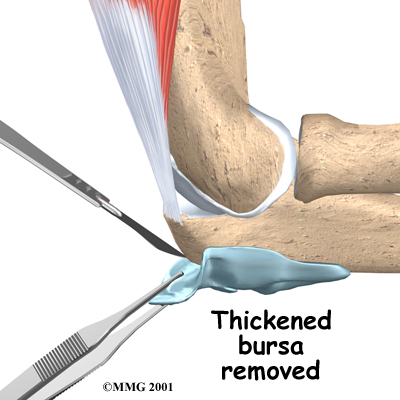

Surgery is sometimes necessary to remove a thickened bursa that has not improved with any other treatment. Surgical removal is usually done because the swollen bursa is restricting your activity.

To remove the olecranon bursa, an incision is made over the tip of the elbow. Since the bursa is outside of the elbow joint, the joint is never entered. The thickened bursa sac is removed, and the skin is repaired with stitches. Your elbow may be placed in a splint to rest the elbow and prevent it from moving for a few days. This allows the wound to begin to heal and prevents bleeding into the area where the bursa was removed.

Incision

Removal of Thickened Bursa

Skin is Repaired

Some types of bursae will grow back after surgery, because the skin needs to slide over the olecranon smoothly. The body forms another bursa as a response to the movement of the olecranon against the skin during the healing phase. If all goes well, the bursa that returns after surgery will not be thick and painful, but more like a normal bursa.